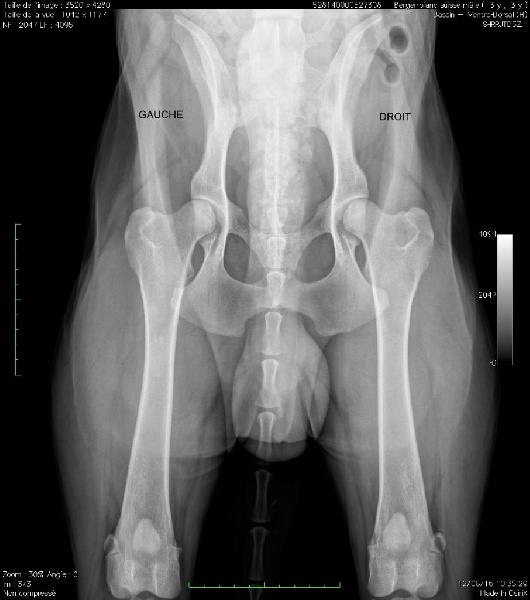

MDR 1 - +/+ Myélopathie dégénérative (MD) - +/+ (Normal) DYSPLASIE HANCHES USA 2° RADIO - EXCELLENT (STADE A1) (OFA)DYSPLASIE COUDES - ED 0DYSPLASIE DES HANCHES, 1° RADIO: - Lecture en France C/B.